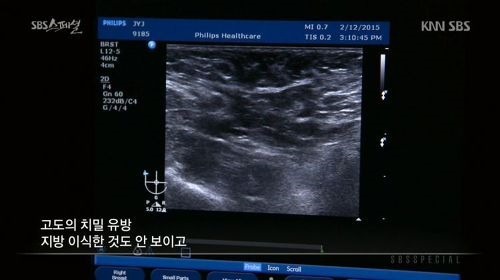

당시 방송에서 장윤주는 가슴을 초음파로 진단했습니다.

장윤주의 가슴 초음파 사진을 살펴본 의사는

"유선 조직이 가슴의 80%이상을 차지하고 있는 고도의 치밀유방이다. 지방 이식한 것도 안보인다. 보면 다 안다. (인공적인 것이)아무것도 없다. 자연산 맞다. 모유 잘 나오겠다"고 진단했습니다.

이에 장윤주는 "저의 가슴 수술논란을 확실히 풀었다"며 기뻐하며 "저도 꼭 모유수유하고 싶다"고 말했습니다.